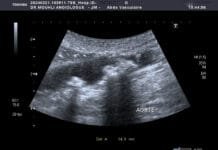

L’aorte : La plus grande artère du corps et les dangers de l’athérosclérose

L’aorte est la plus grosse artère du corps. Partant du cœur, elle achemine le sang vers les jambes en passant par le thorax et l’abdomen. Elle décrit d’abord un trajet ascendant puis effectue un virage (crosse) où naissent les artères à destination des bras et du cerveau. Elle descend ensuite dans le thorax en vascularisant la moelle épinière. Une fois au niveau du diaphragme, elle devient l’aorte abdominale où le sang est distribué dans les artères du tube digestif (tronc cœliaque donnant les artères hépatique et splénique, artère mésentérique supérieure, artère mésentérique inférieure) et des reins.Les thromboses aortiques sont le plus souvent liées à la présence de lésions athéromateuses au sein de la paroi aortique chez des patients avec des facteurs de risques cardio-vasculaires. De rares cas surviennent sur artère saine et sont alors considérés comme « isolés ».L’athérosclérose est responsable de nombreuses maladies cardio-vasculaires qui représentent la première cause de mortalité dans le monde. QU’EST-CE QUE L’ATHÉROSCLÉROSE ? L’Athérosclérose ou artériosclérose correspond à un dépôt de graisses formant une plaque d’athérome qui rétrécit le passage du sang. QUELLES SONT LES CONSÉQUENCES DE L’ATHÉROSCLÉROSE ? Les conséquences de la plaque d’athérome sont multiples dont la rupture à l’origine d’accident vasculaire grave. L’athérosclérose peut toucher différents organes. Un rétrécissement d’aorte Un rétrécissement des artères carotides peut entraîner un accident vasculaire cérébral. En cas d’atteinte des artères des jambes, on parlera d’artériopathie oblitérante ou artérite des membres inférieurs. L’atteinte des artères coronaires peut entraîner des infarctus du myocarde.Le mode de révélation clinique de la thromboseClaudication fessiére ;pieds froids et absence de pouls périphérique Il s’agit du cas typique d’une patiente présentant une sténose de l’aorte abdominale sous-rénale (sténose de l’aorte basse) à extension iliaque, découverte à l’occasion de la persistance de douleurs dorsales à irradiation fessière.une ischémie aiguë de membre dans 8 cas sur 10. écho-Doppler artériel un scanner thoraco-abdominal injecté, Les cas survenant sur artère saine sont difficiles à dénombrer et le terme de thrombus « isolé » est peut-être employé par défaut. L'hypothèse d'une lésion athéromateuse focale isolée induisant un thrombus, ou des pathologies inflammatoires diagnostiquées sur l'examen anatomopathologique du thrombus l'illustrent.POURQUOI UN ÉCHODOPPLER ?